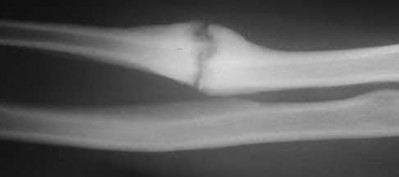

4. # After undergoing the treatment seen in Figure A, when should a patient be expected to safely operate the brakes of an automobile?

Corrent answer: 4

Figure A shows a patient after an open reduction and internal fixation of a bimalleolar ankle fracture.

Egol et al showed that by nine weeks, the total braking time of patients who had undergone fixation of a displaced right ankle fracture returns to the normal, baseline value.

Egol et al, also found that appropriate braking time returns at a point 6 weeks after initiation of weightbearing after treatment of lower extremity long bone and periarticular fractures, as examined with a driving simulator. No differences were seen in return of braking time between periarticular fractures and long bone injuries.